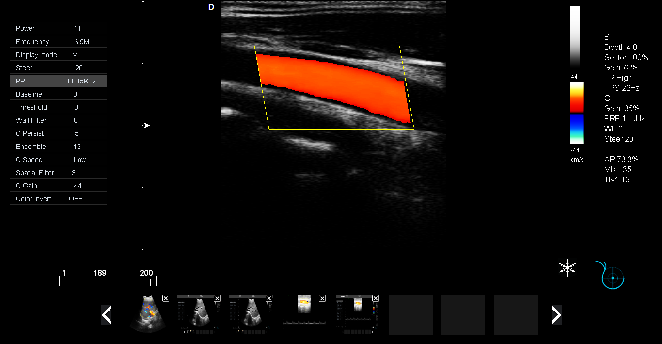

P5-VET便攜獸用彩超機(jī)頸動(dòng)脈檢查圖

頸動(dòng)脈血流:

頸動(dòng)脈彩超是診斷、評(píng)估頸動(dòng)脈壁病變的有效手段之一,在動(dòng)脈粥樣硬化的流行病學(xué)調(diào)查和對(duì)動(dòng)脈粥樣硬化預(yù)防、治療試驗(yàn)的有效性評(píng)價(jià)中起著關(guān)鍵作用。

頸動(dòng)脈彩超不僅能清晰顯示血管內(nèi)中膜是否增厚、有無(wú)斑塊形成、斑塊形成的部位、大小、是否有血管狹窄及狹窄程度、有無(wú)閉塞等詳細(xì)情況, 并能進(jìn)行準(zhǔn)確的測(cè)量及定位,還能對(duì)檢測(cè)動(dòng)脈的血流動(dòng)力學(xué)結(jié)果進(jìn)行分析。